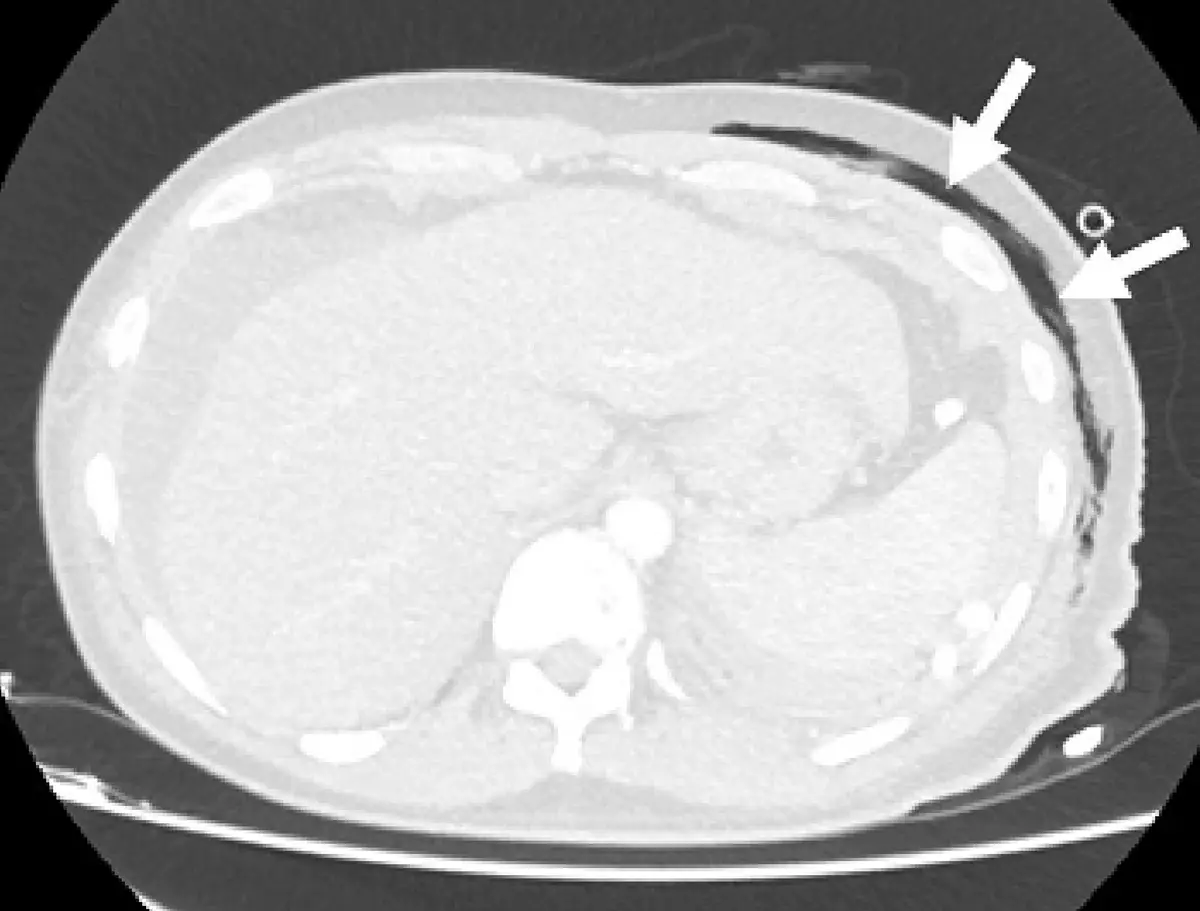

本題附圖為胸部 CT 橫切面影像,影像特徵如下:

- 整體外觀:影像以淡灰色調為主,背景接近白色,骨骼(肋骨、椎體)呈明顯亮白色。

- 肺實質:肺部顯示為深灰至黑色,空氣腔(-1000 HU)呈暗黑色,與軟組織形成明顯對比——這是**肺窗(lung window)**的典型表現。

- 軟組織:胸壁肌肉和縱隔結構呈較淡灰白色,細節分辨度低(肺窗對軟組織解析度較低)。

- 箭頭指示:左側胸壁外側有兩個白色箭頭,指向一個細小圓形低密度結構(可能為氣胸、皮下氣腫或胸壁病灶)。

- 判讀:影像整體呈現為肺窗(lung window)——寬視窗(wide window width ≈1500–2000 HU)搭配低(負值)視窗中心(level ≈-600 至 -700 HU),使空氣顯示為黑色、肺組織灰色、軟組織偏白。

影像判讀結論:此影像為肺窗設定,最符合 window 1700,le